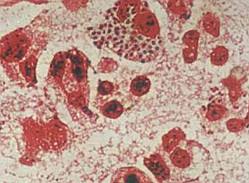

淋病是淋病奈瑟菌(简称淋球菌)引起的以泌尿生殖系统化脓性感染为主要表现的性传播疾病。淋球菌为革兰阴性双球菌,离开人体不易生存,一般消毒剂容易将其杀灭。淋病多发生于性活跃的青年男女。那么得了淋病会出现什么样的症状,下面我们请北京京城皮肤医院的专家给大家讲解一下。